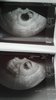

Cześć dziewczyny jestem po dzisiejszej wizycie u gina :) Dzidzie już ładnie widać nie tylko taka kropke jak 2 tyg temu :) Z OM i z USG 9tyg i 2 dni wiec wszystko jest dobrze :) Kolejna wizyta 26 stycznia i 18 stycznia mam usg prenatalne

Załączniki

• 26180012_1395006470628960_1763293752_o.jpg